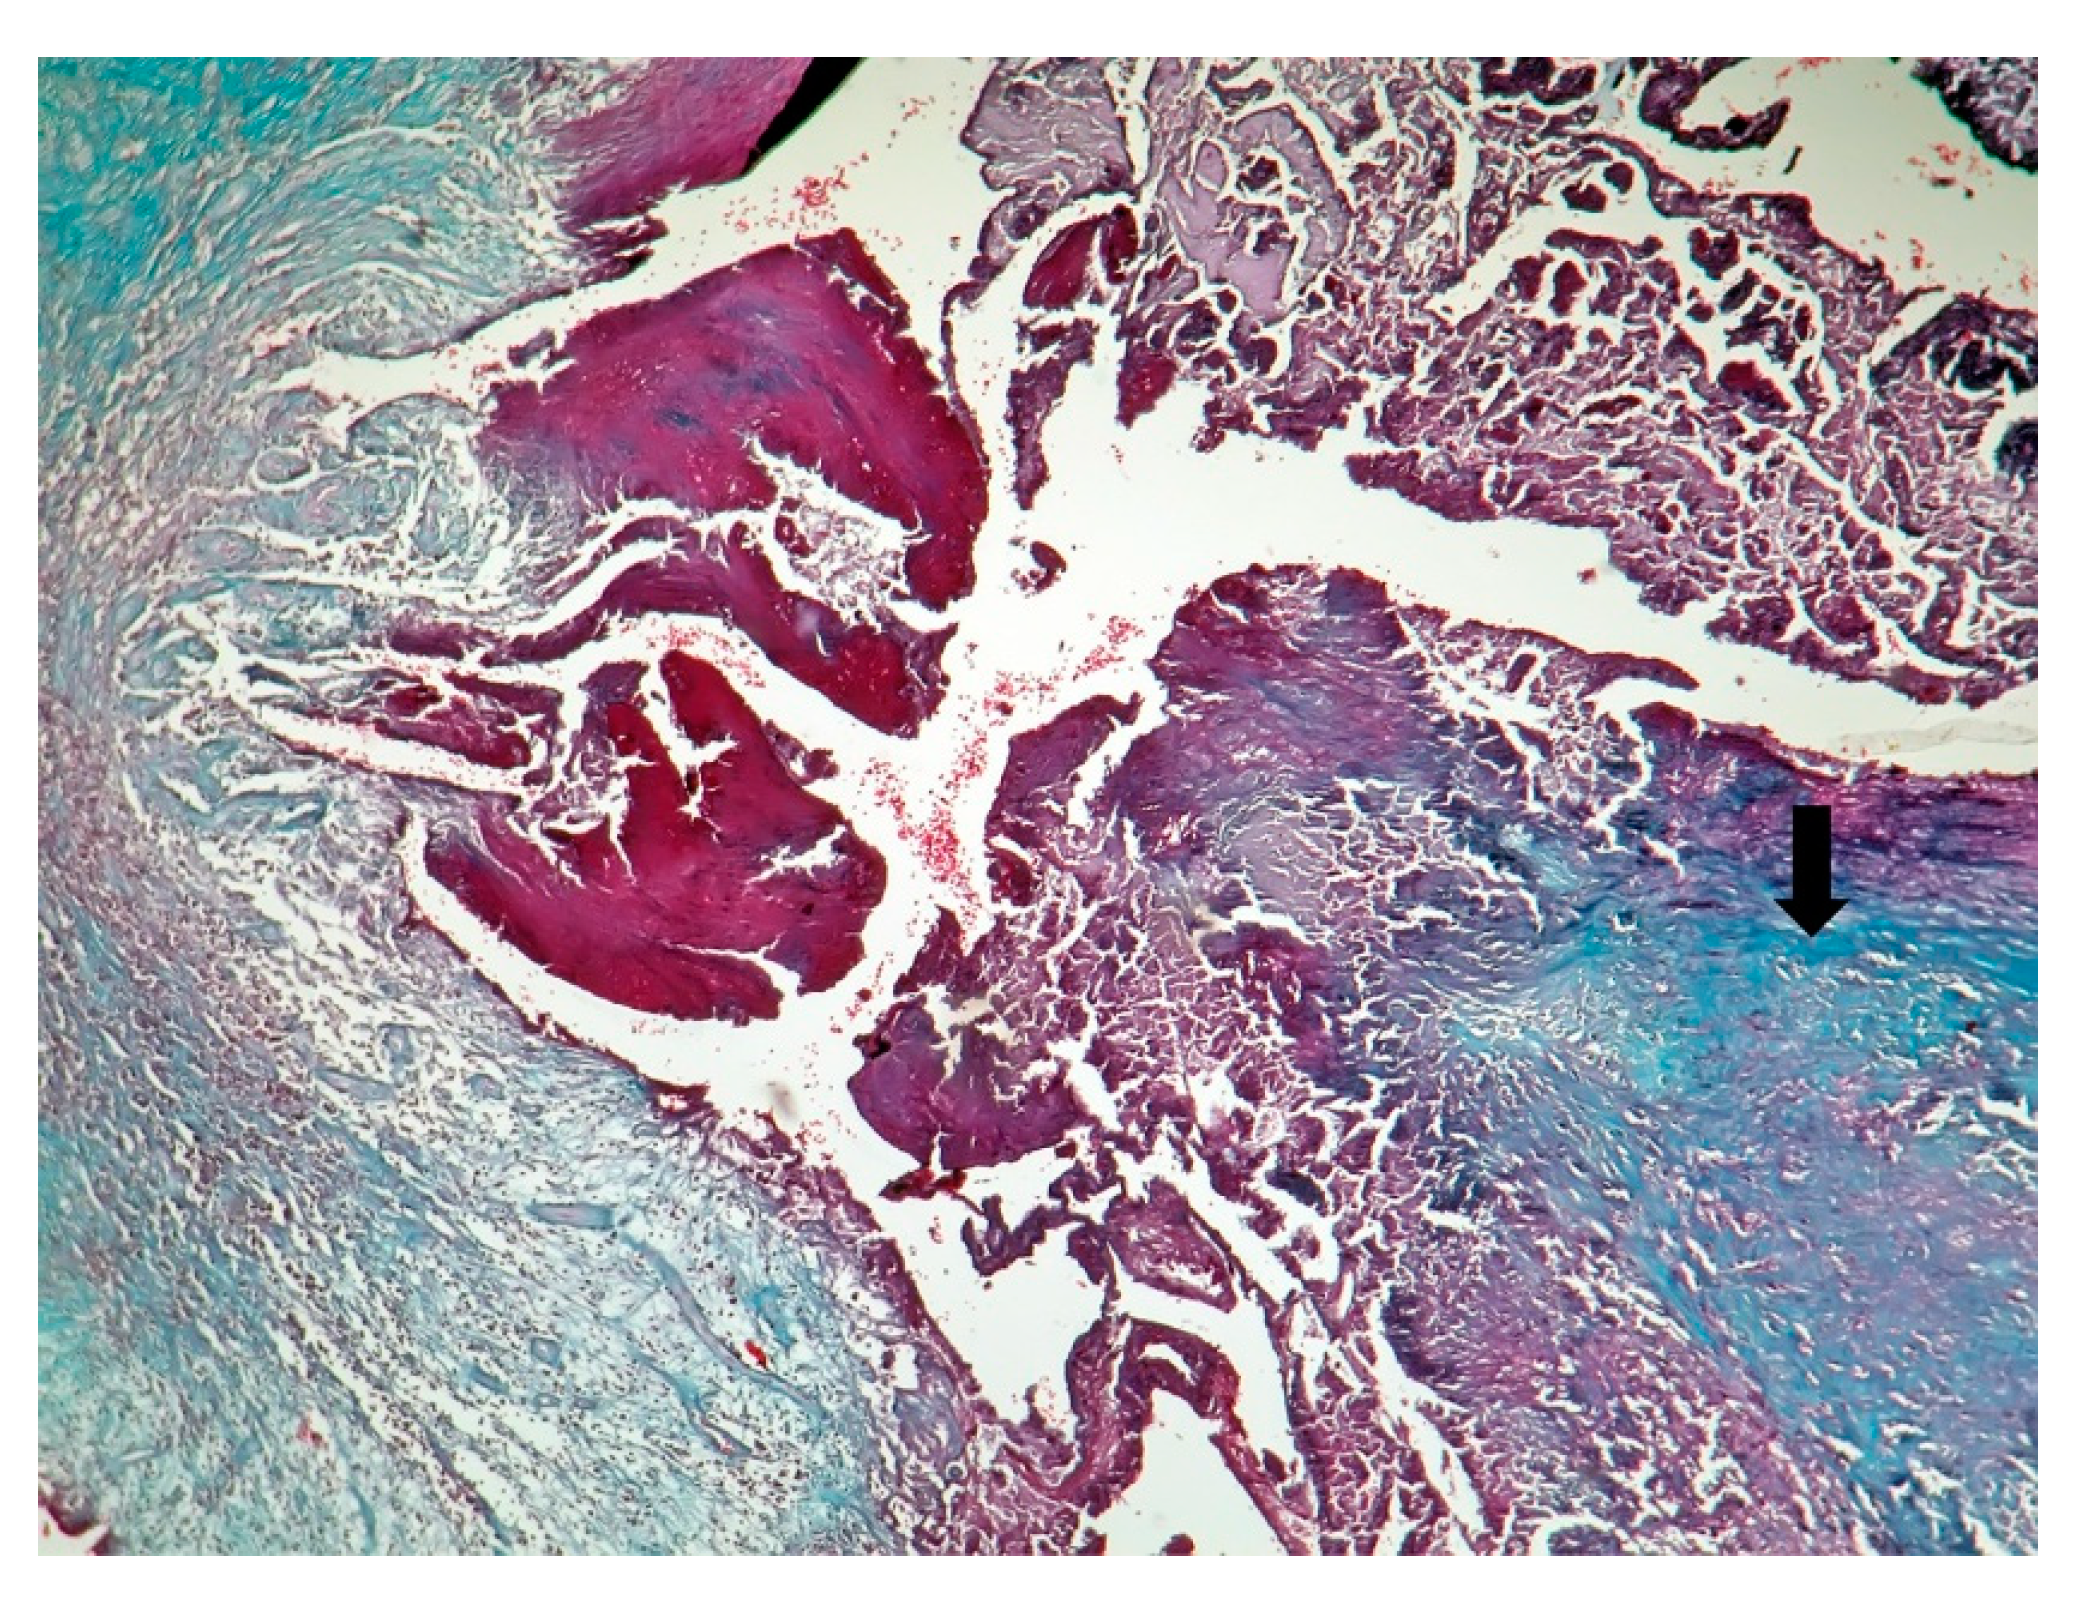

| Macroscopic | Mural trombi, Endocardial fibrosis [23] Monovalvular involvement Mixoid degeneration Valve ulceration or fibrinous mass No fibrin valve deposits [24,25] | Small, warty, sessile vegetations on valve flow surface [26] | Large or small vegetations on valve flow surface [27] | Small or absent vegetations, with a smooth nodular aspect [13] |

| Microscopic | Mixoid degeneration, mixed inflammatory pattern, granulomas, thickening of the small vessels wall [23] | Platelets, fibrin, red blood cells Repetitive process with fibroblastic organization and neovascularization [28] | Fibrin, polymorphonuclear inflammation and some bacterial colonies [29] | Minimal mononuclear inflammation, histiocytes, foamy macrophages and mild vascularization [30] Granulomas [31] Microabscesses; usually no microorganism, sometimes coccoid inclusions [23] Fibrosis, thrombosis and calcifications, mimicking degenerative damage [32] |